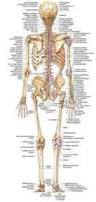

1181 × 1300 - gimolimpo.com

{"id":"Rohz-pKMmS4_0M:","isu":"gimolimpo.com","itg":0,"ity":"jpg","oh":1300,"ou":"http://www.gimolimpo.com/PAGINA%2062/musculosdorsales.jpg","ow":1181,"pt":"ANATOMIA

HUMANA","rid":"KhRkfq-OMAvQ7M","rmt":0,"rt":0,"ru":"http://www.gimolimpo.com/Paginas/ANATOMIA%20HUMANA.htm","s":"Visión

189 × 397 - gimolimpo.com

{"id":"Jzk23AG6PG4tMM:","isu":"gimolimpo.com","itg":0,"ity":"jpg","oh":397,"ou":"http://www.gimolimpo.com/Paginas/anatomia_archivos/image013.jpg","ow":189,"pt":"ANATOMIA

HUMANA","rid":"KhRkfq-OMAvQ7M","rmt":0,"rt":0,"ru":"http://www.gimolimpo.com/Paginas/ANATOMIA%20HUMANA.htm","s":"Esqueleto